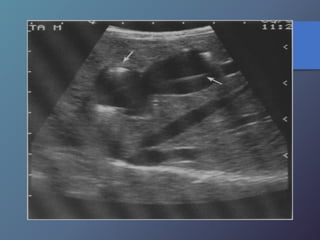

Abscesos Hepáticos Bacterianos

• Extensión directa por vía biliar-portal o

traumática.

• Características ecográficas variables

hipoecoicas.

• Artefactos de reverberación por

presencia de gas.

• Tabiques internos.

• Pared variable desde bien definida a

irregular y gruesa.